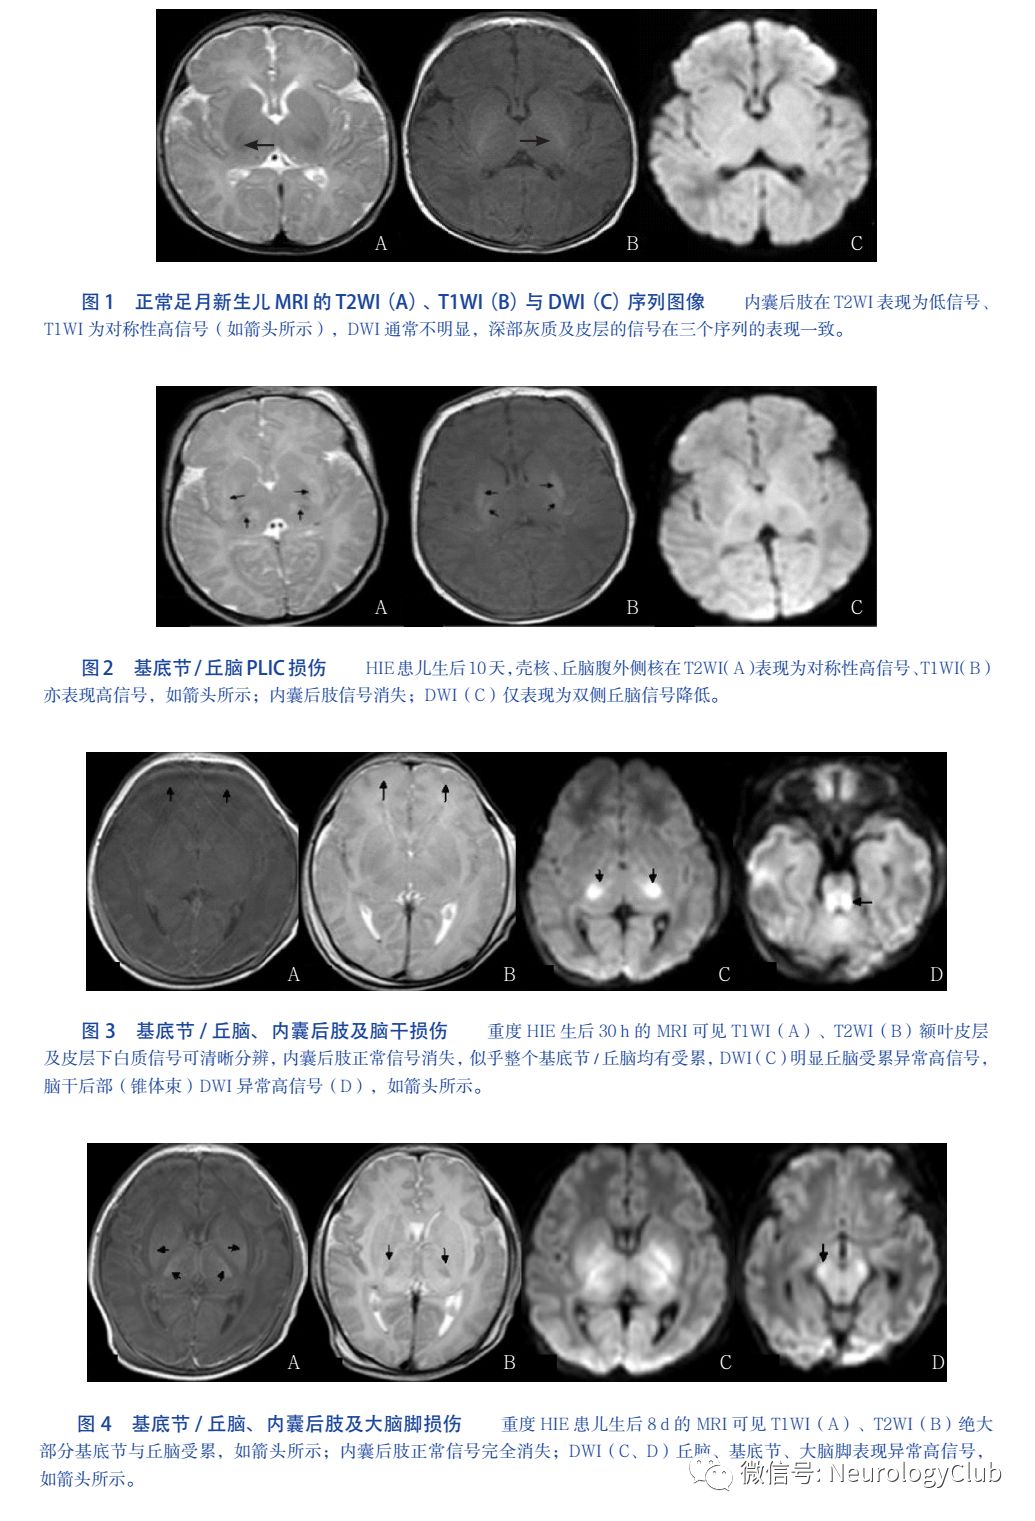

3.1 丘脑基底节+内囊后肢受累

急性完全性窒息通常使丘脑最先受累,特别是丘脑腹外侧核;基底节最易受累核团为壳核,通常苍白球很少受累HIE急性期T1WI表现为高信号,T2WI为低信号,DWI为高信号;慢性期表现为萎缩或坏死:T2WI表现为高信号,而T1WI信号正常或降低,DWI正常信号或低信号。依据受累范围划分损伤的严重程度,严重者丘脑或基底节完全受累,常伴有罗兰氏区周围皮层、间脑和脑干受累。内囊后肢(posterior limb of internal capsules,PLIC)正常情况下为T1WI高信号、且接近内囊的膝部,T2WI为低信号至少占整个后肢的1/3PLIC受累可表现为:(1)可疑受累:PLIC在T1WI/T2WI信号减低或出现不对称性改变;(2)明显受累:PLIC在T1WI/T2WI信号出现反转。见图1-4。